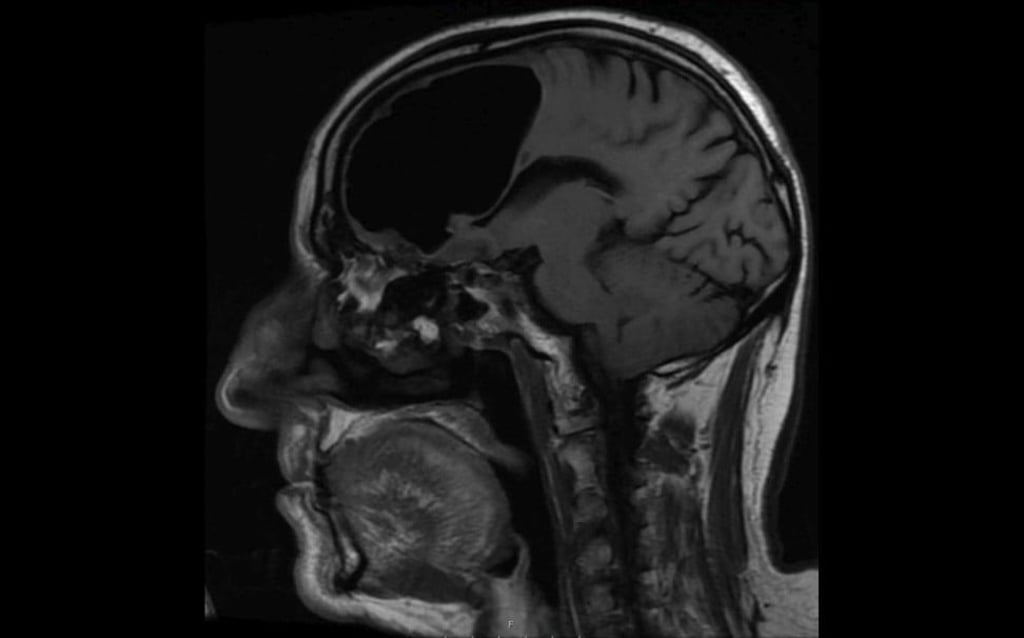

China has launched a plan to develop the world’s most powerful brain scanner, one that could generate an extremely strong magnetic field to observe for the first time the structure and activities of every neuron in a living human brain.

The projected scanner would not only produce a snapshot with details far beyond what existing instruments can provide, but also track various types of chemical agents including sodium, phosphorus and potassium that pass critical signals along neural fibre networks to study consciousness and brain-related diseases such as Parkinson’s.